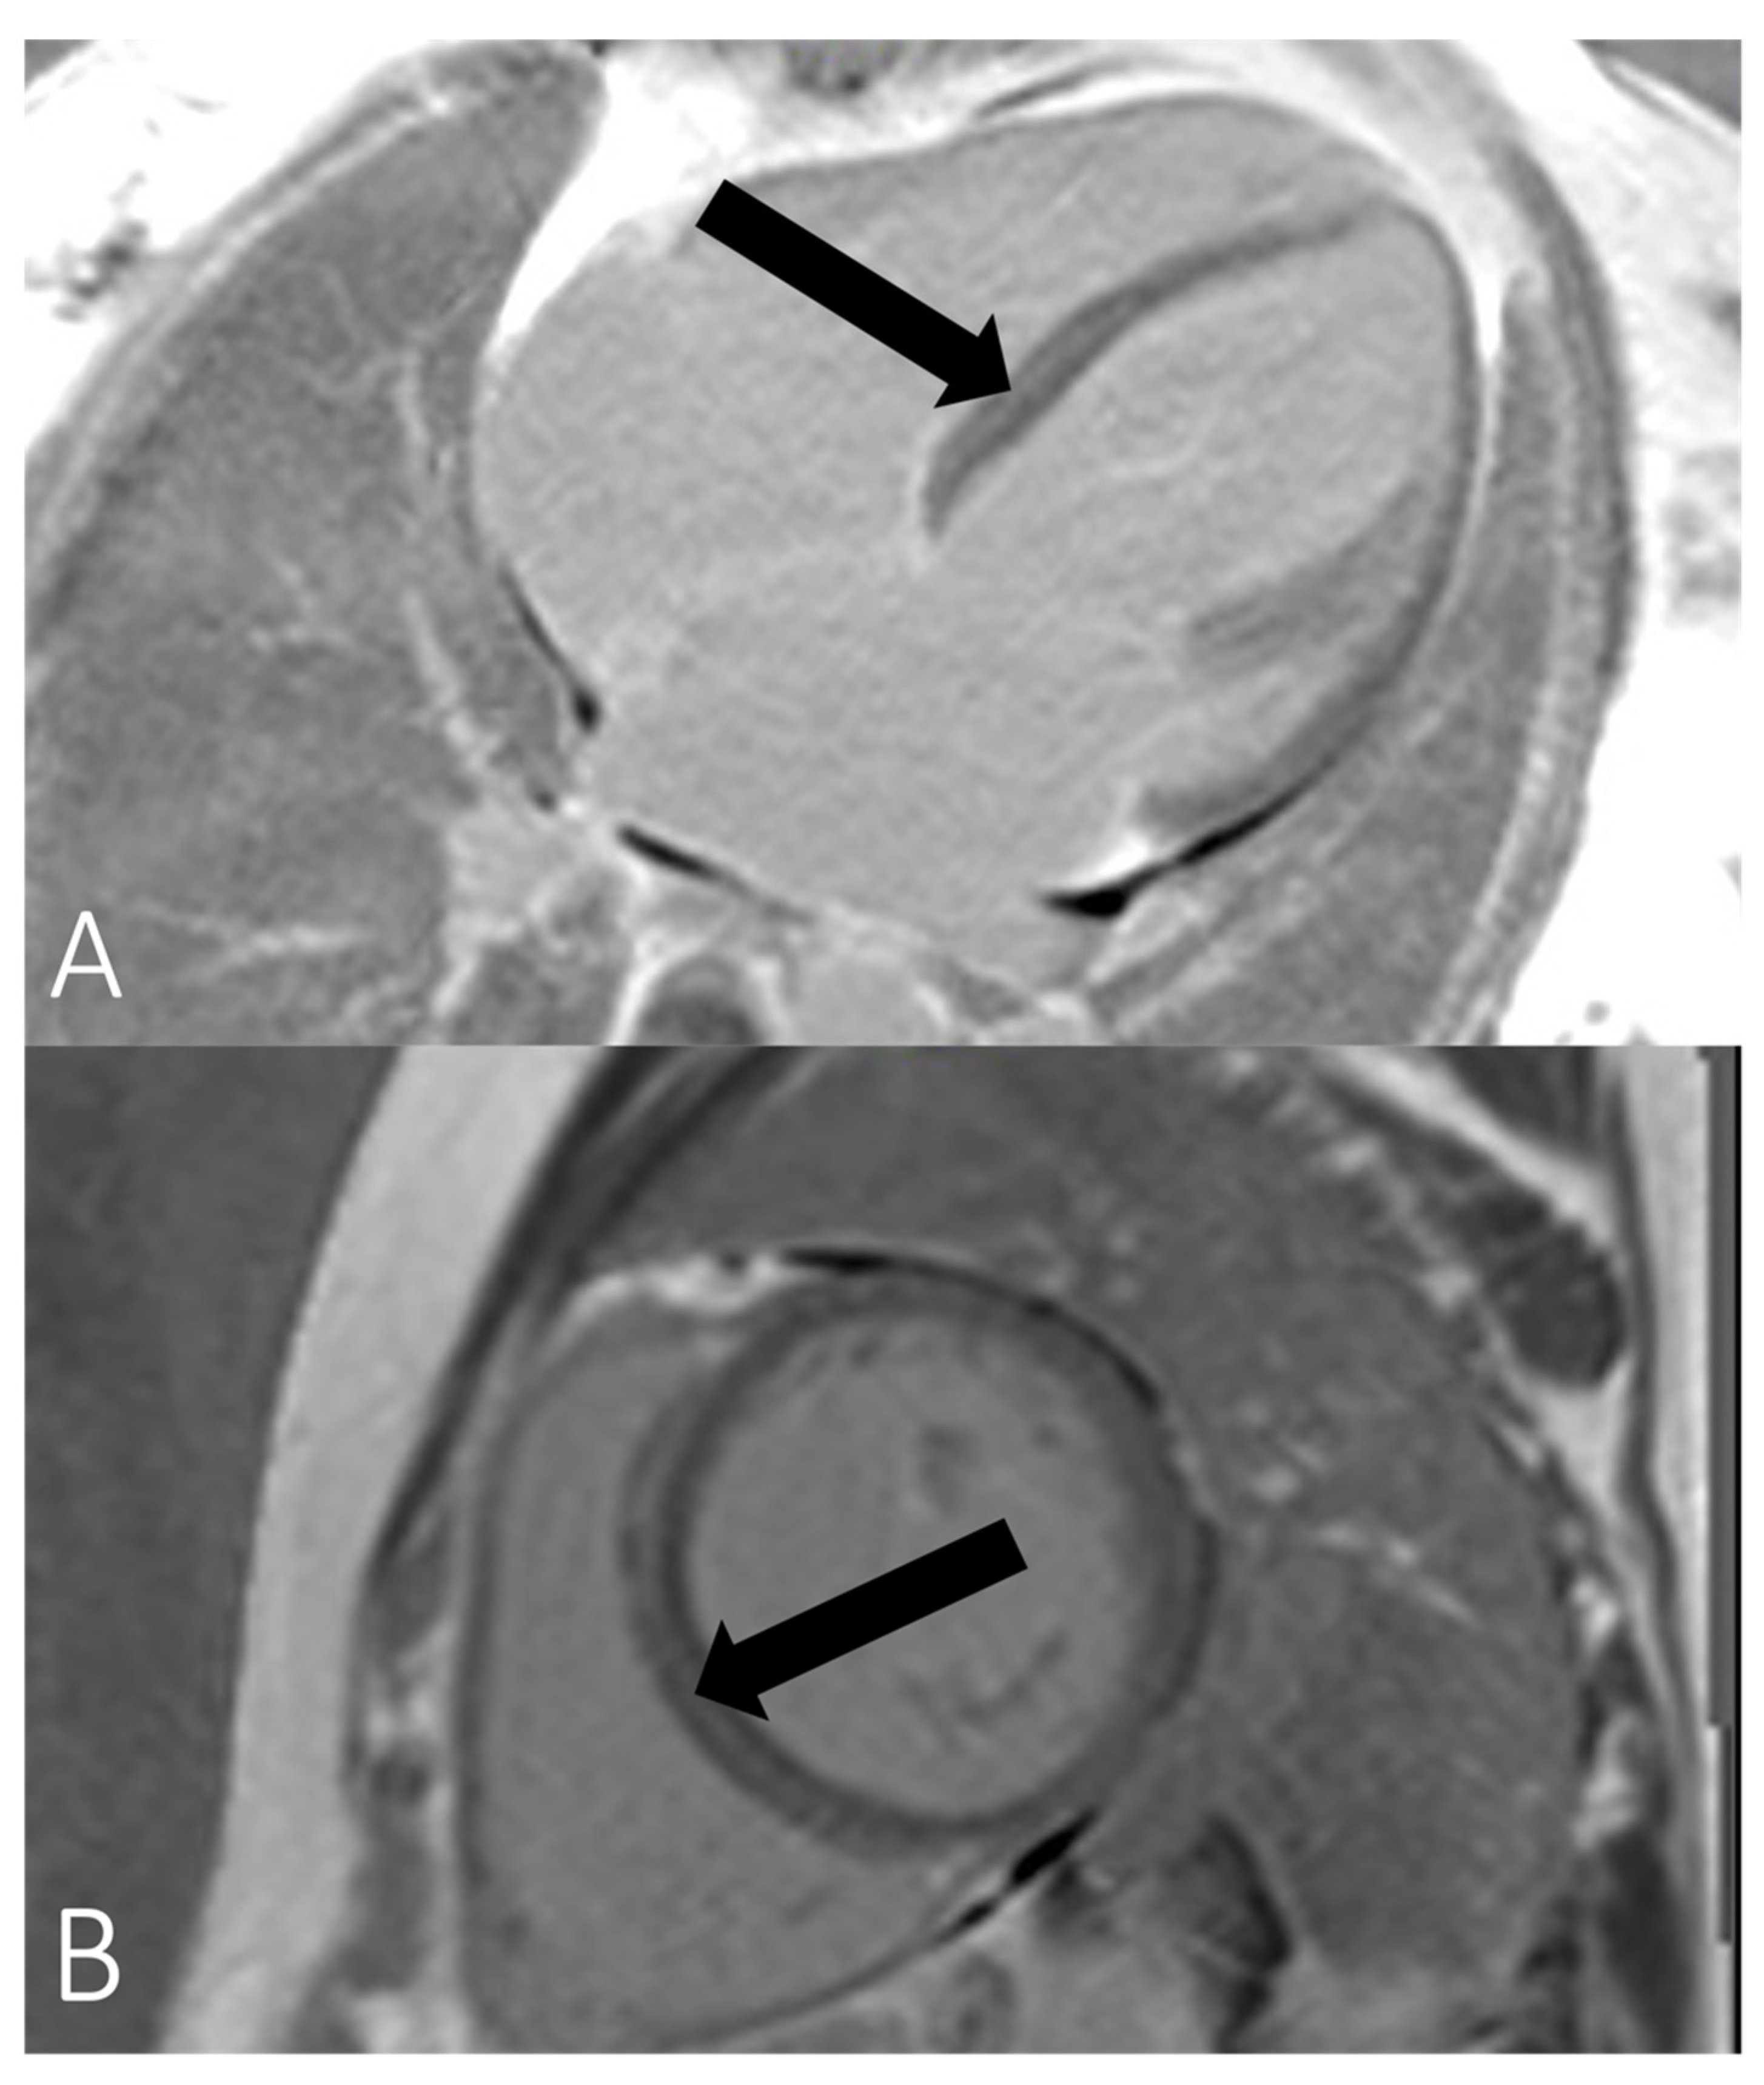

Figure 3.

Magnetic resonance imaging (MRI) samples of patient III:3. Septal midwall late-gadolinium enhancement (LGE) in (A) long-axis view and (B) short axis view, indicated by black arrows.

The imaging features of LMNA cardiomyopathy are often not discernible from other forms of DCM. Left ventricular function of LMNA mutation carriers and DCM does not significantly differ from non-LMNA DCM, whereas LVEDD tends to be lower than in non-LMNA DCM [1]. However, direct comparison of echocardiographic parameters with non-LMNA DCM is scarce and LMNA cardiomyopathy may also adopt the arrhythmogenic right ventricular cardiomyopathy phenotype [35]. LMNA cardiomyopathy show typical midmyocardial septal late-gadolinium enhancement (LGE) on cardiac MRI [29,36,37,38] as has been seen in patients 2 and 3 in our study. LGE presence seems more pronounced in DCM with LMNA mutation than in non-LMNA-DCM [37]. Holmström et al. described the presence of LGE in 88% of 17 mutation carriers with DCM, whereas Marco et al. described the presence of LGE in 44% of cases in a meta-analysis of 1305 patients with non-LMNA-DCM [37,39]. Augusto et al. showed a similar distribution of scar tissue mainly in the midwall septum and at the inferior insertion point of the right ventricle in most LMNA-carriers with DCM; however, findings failed to discriminate different DCM genotypes [40]. It has been hypothesized that septum fibrosis may be an underlying mechanism for conduction disturbances [6]. Peretto et al. could demonstrate a significant association between the presence of LGE and malignant arrhythmic events in a cohort of 41 patients with an LMNA mutation [38]. Interestingly, no patient without LGE developed VT or ventricular fibrillation at a mean follow-up of 10 years [38]. However, the small study sample may hamper transferability, and further studies are required to elucidate the role of LGE and its possible value for current risk scores.